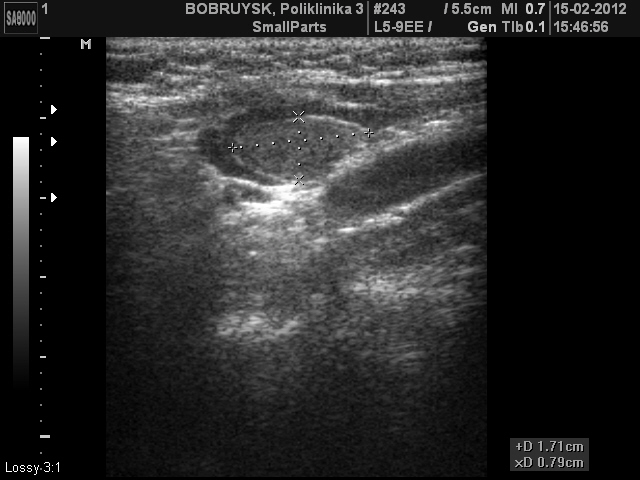

Вот такой ультразвуковой случай образования в проекции щитовидной железы.

Пациентка 66 лет. Жалоб не предъявляет

Стоит на учете у эндокринолога, диагноз не помнит, но говорит узел какой то года три назад, пунктировали, но результатов не знает и не помнит.

ADENOMA_5.JPG

ADENOMA_11.JPG

Первое впечатление - ХАИТ, псевдоузловая форма.

Я конечно же не "свадебщик", по этому в данном случае, рассматриваю вариант с аденомой паращитовидной железы. Хотя структура самой щитовидной железы, которая мной отражена не достаточно хорошо в ролике, действительно похожа на АИТ.

Но доказать это с помощью только УЗИ сложно, если не невозможно.

Пациентке в заключении рекомендовал пункцию, попробую проследить за этим случаем.